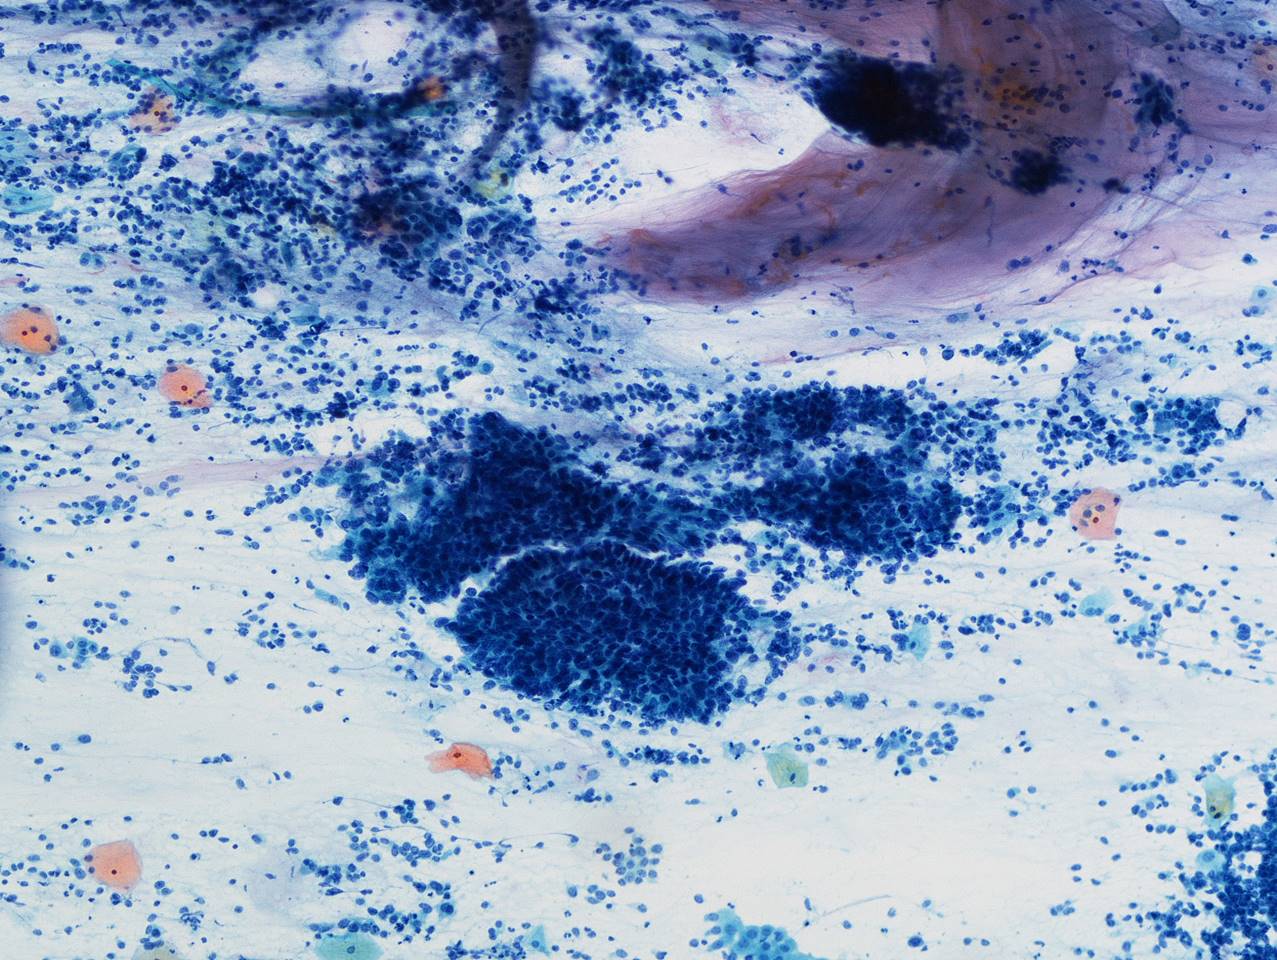

細胞診所見

背景に壊死物質は認められなかった。その中に偏在性核で核クロマチン増量を示す腺系異型細胞の不整形集塊を認めた。柵状配列や腺管構造もみられ上皮内腺癌を疑う細胞と考えた。またN/C比が高く細顆粒状の核クロマチンを有する傍基底型核異常を疑う細胞もみられた

[まとめ] 稀な子宮頸部腫瘍の症例を経験した。細胞診スメア標本では2種類の異なる異型細胞を認識することはできたがLBC標本では難しく神経内分泌癌との推定には至らなかった。腺系病変を疑う症例では、異なる成分の混在を念頭に注意深く鏡検することが重要と考えた。

[まとめ] 稀な子宮頸部腫瘍の症例を経験した。細胞診スメア標本では2種類の異なる異型細胞を認識することはできたがLBC標本では難しく神経内分泌癌との推定には至らなかった。腺系病変を疑う症例では、異なる成分の混在を念頭に注意深く鏡検することが重要と考えた。